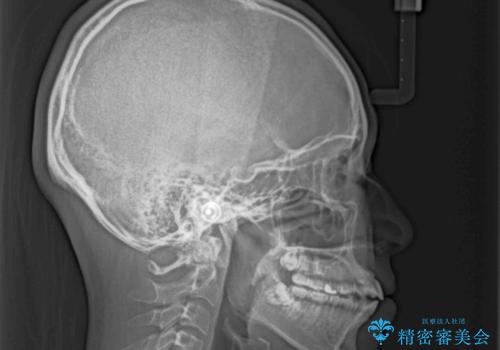

- 口元の突出感と上下前歯のズレを気にして来院された患者様です。

舌の突出癖により上下の前歯は非接触となっている状態でした。

突出感改善のため、上下左右の第一小臼歯4本を抜歯し、ワイヤー装置にて矯正治療を行うこととしました。